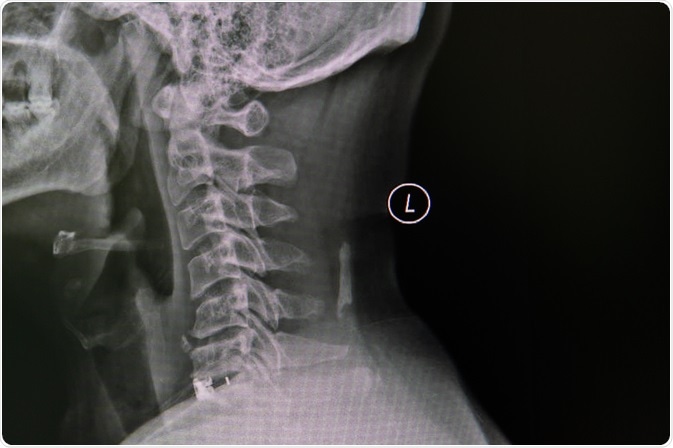

Cervical spondylosis is caused by abnormal wear on the bones that make up the spine (vertebrae) in the neck region.

Image Credit: Nuiza11/Shutterstock.com